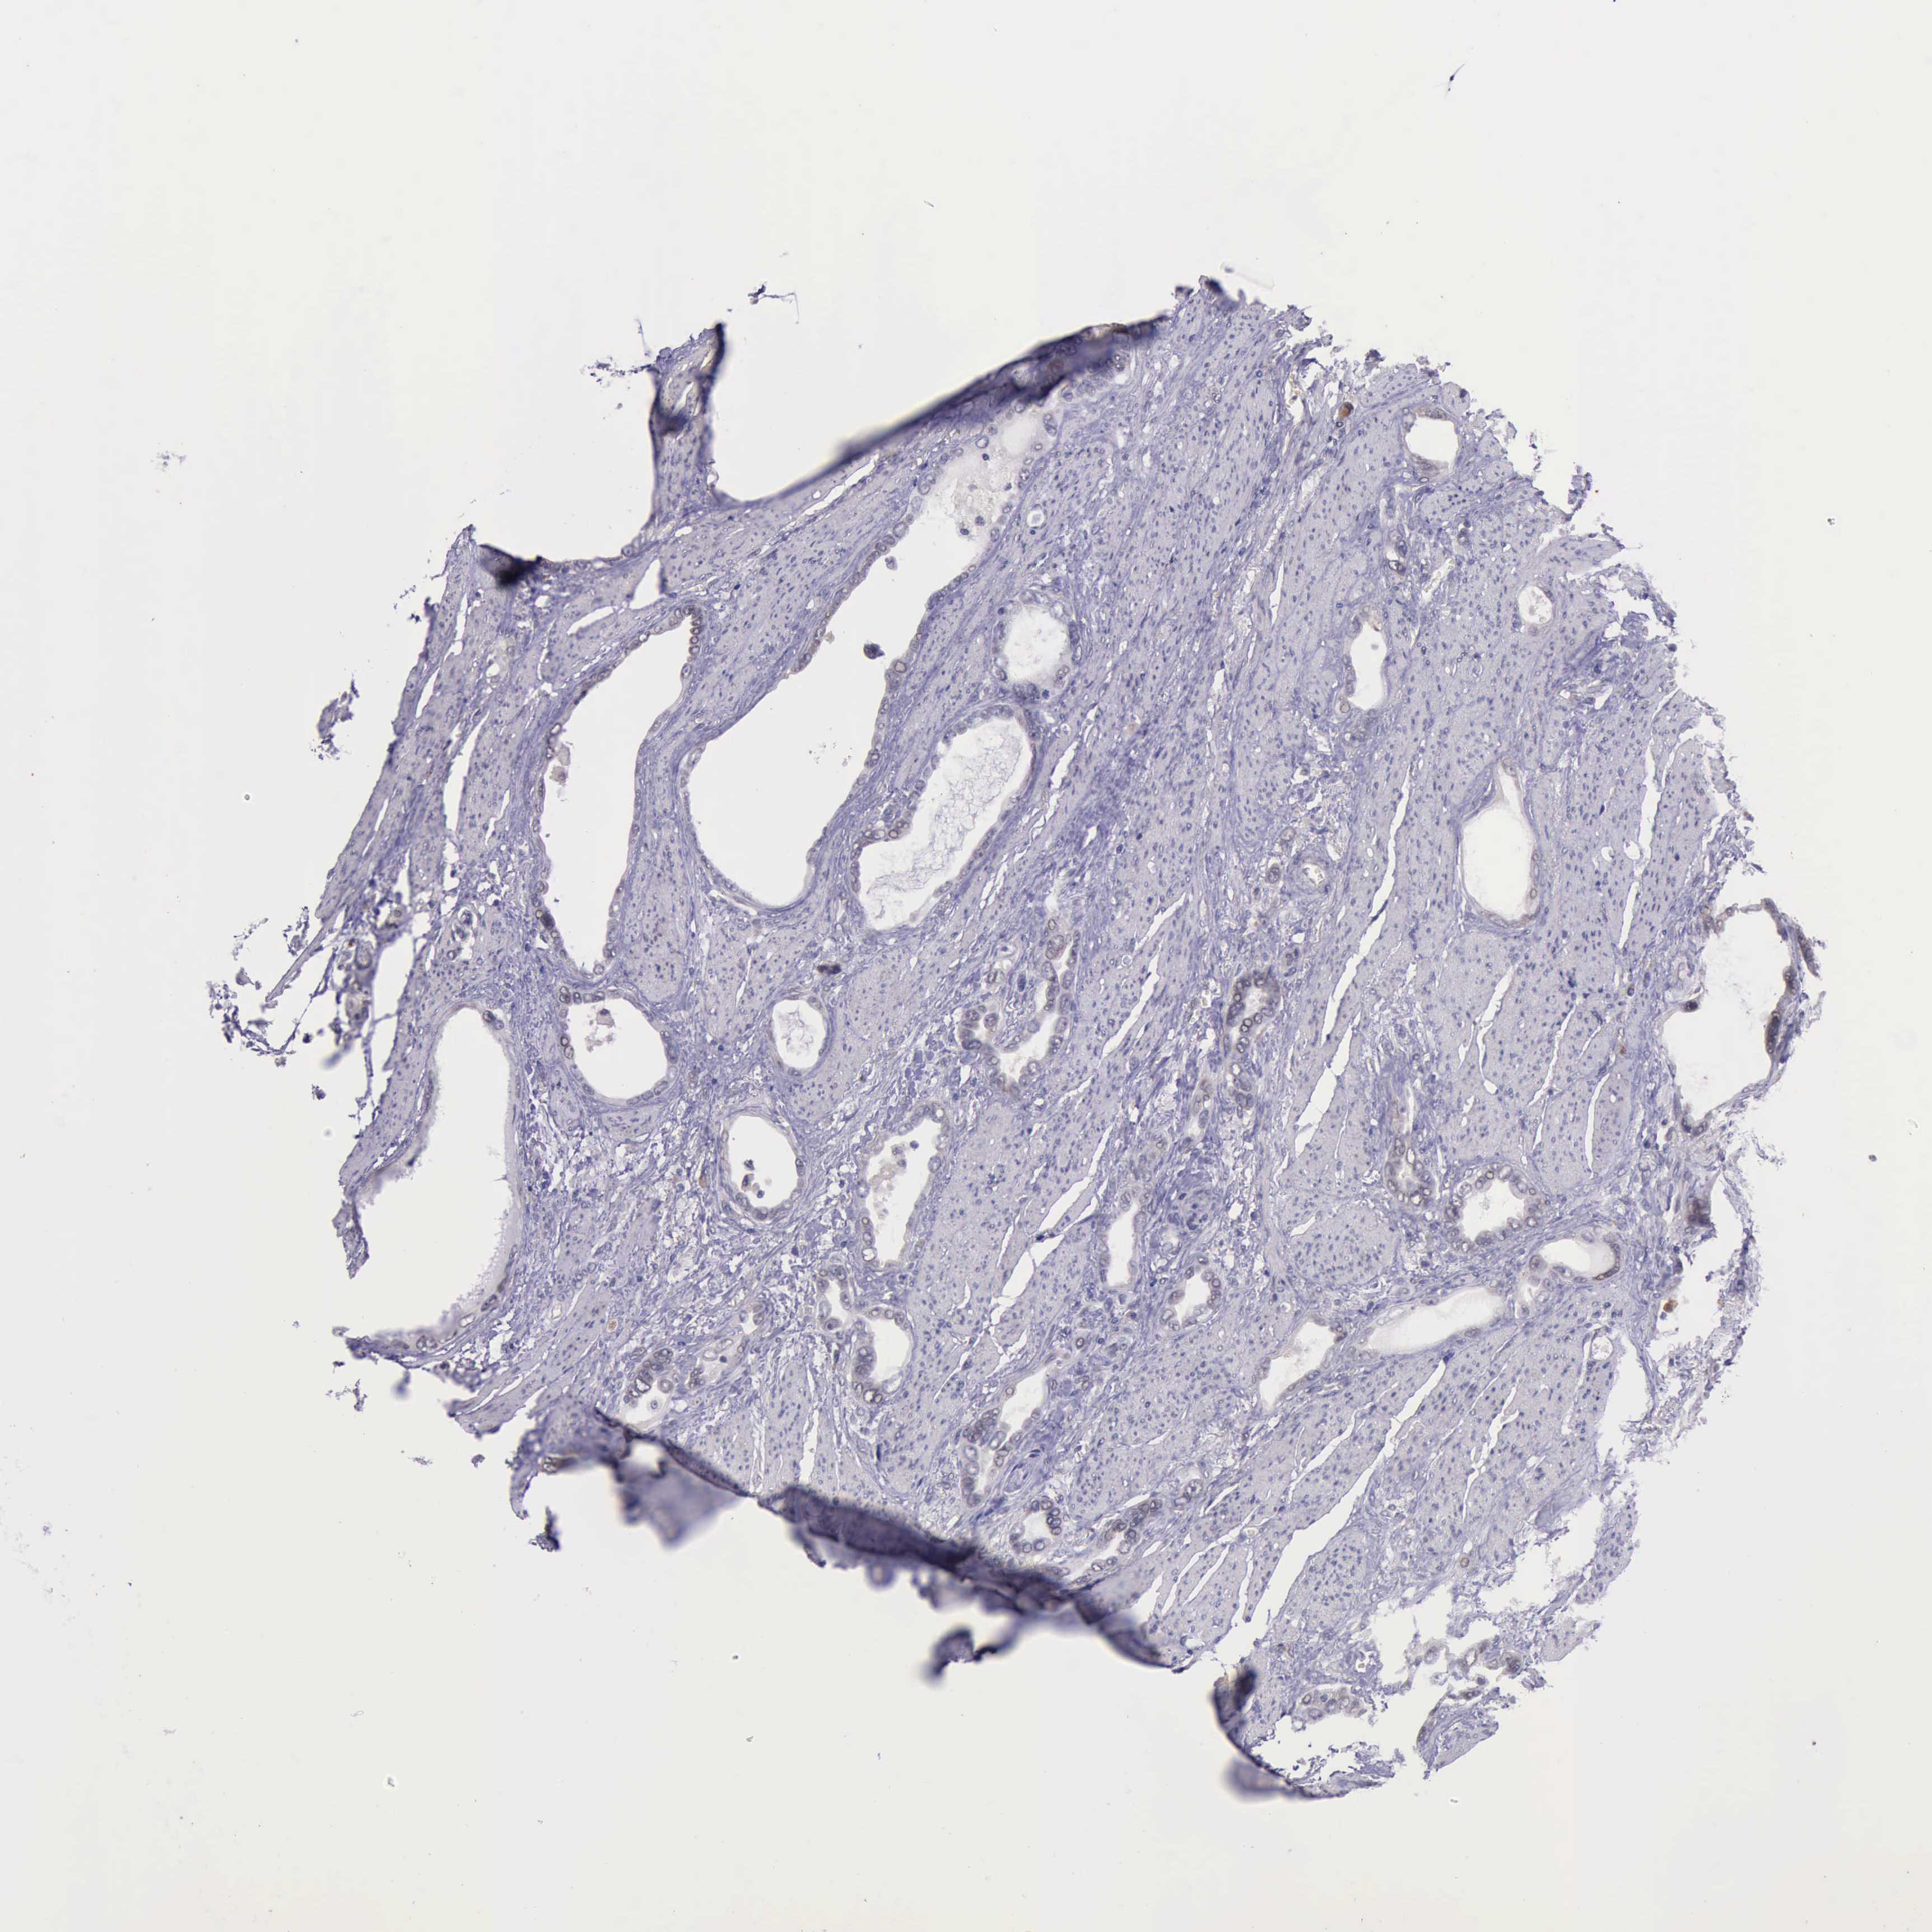

STOMACH CANCER - Protein expressioni

A mouse-over function shows sample information and annotation data. Click on an image to view it in a full screen mode. Samples can be filtered based on level of antibody staining by selecting one or several of the following categories: high, medium, low and not detected. The assay and annotation is described here.

Note that samples used for immunohistochemistry by the Human Protein Atlas do not correspond to samples in the TCGA dataset.

Antibody stainingi

Antibody staining in the annotated cell types in the current human tissue is reported as not detected, low, medium, or high, based on conventional immunohistochemistry profiling in selected tissues. This score is based on the combination of the staining intensity and fraction of stained cells.

Each image is clickable and will lead to virtual microscopy that enables deeper exploration of all samples and also displays staining intensity scores, fraction scores and subcellular localization as well as patient and tissue information for each sample.

Antibody HPA001208

Staining

High

Medium

Low

Not detected

Intensity

Strong

Moderate

Weak

Negative

Quantity

>75%

75%-25%

<25%

None

Location

Nuclear

Cytoplasmic/membranous

Cytoplasmic/membranous,nuclear

Adenocarcinoma, NOS